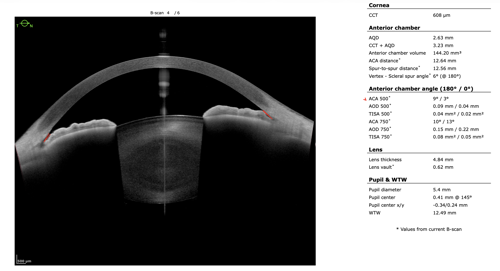

To refine surgical candidacy, anterior segment imaging was performed using the Heidelberg ANTERION SS-OCT. High-resolution imaging clearly demonstrated the following:

- A visually clear crystalline lens, not meeting criteria for cataract extraction

- Markedly narrow angles at iris insertion

- Angle measurements in the single-digit degrees

These findings supported LPI as the most appropriate intervention.